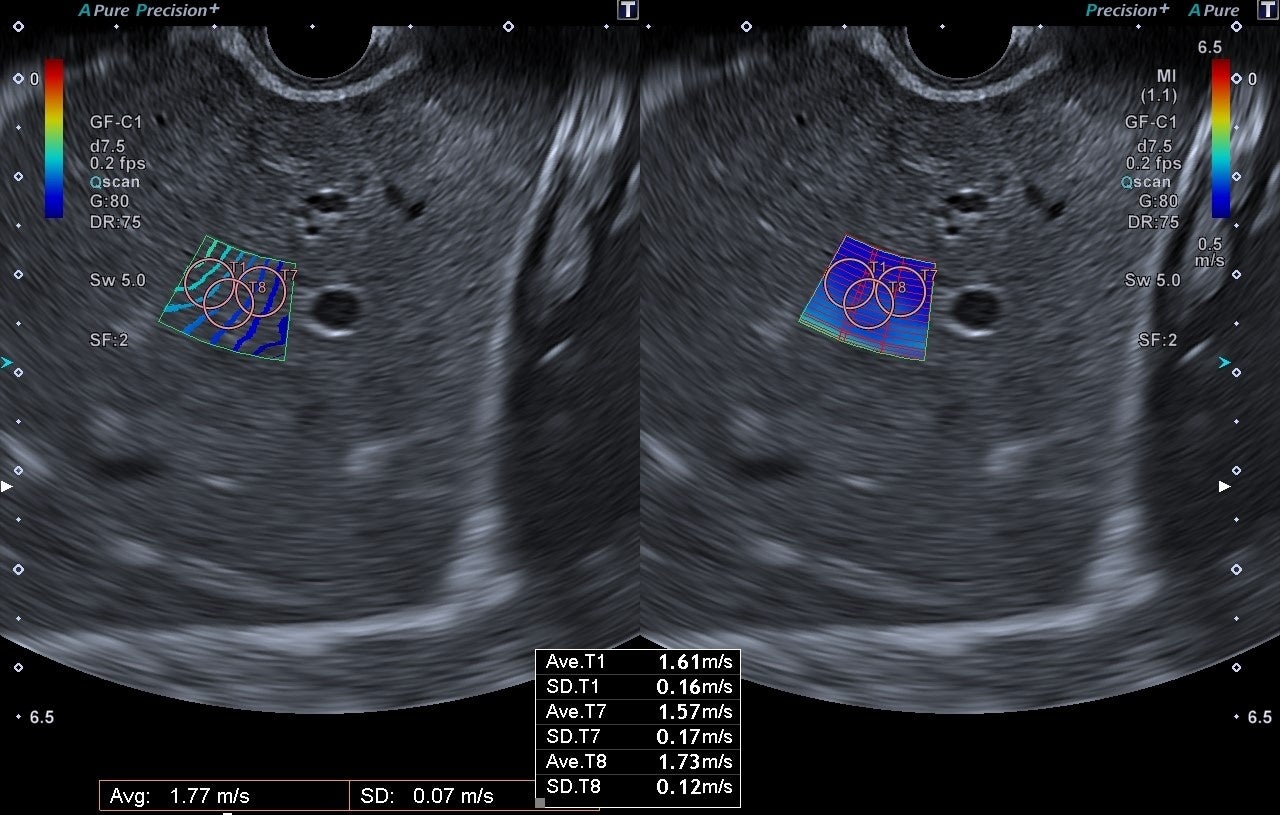

EUSをサポートする多彩な機能を搭載することで、信頼性の高い診断・治療方針の決定をサポートします。キヤノンメディカル独自技術であるSMI(Superb Micro-vascular Imaging)は、微細で低速な血流を捉える血流イメージングです。カラードプラ※1は描出困難であった低流速血流を高感度、高分解能、高フレームレート※2、低アーチファクト※3に描出できるため、超音波画像下で穿刺を行う場合でも、より安全な手技をサポートします。また、EUSで病変の炎症度や良悪性などを診断する際、病変組織の硬さに関する情報が重要な判断材料になります。SWE(Shear Wave Elastography)は組織の硬さを数値やカラーマップで表示する技術のため、より客観的な硬さの評価が可能です。

SMI SWE